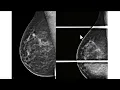

Olá eu sou professor Rodrigo Jales do serviço de imagem do Hospital da Mulher da Unicamp hoje eu quero mostrar para vocês é essa mamografia trata-se de uma paciente com cerca de 60 anos com antecedência de ter tratado um câncer na mama esquerda com cirurgia conservadora veja que algumas alterações cicatriciais algumas distinção arquitetural nos quadrantes superiores no prolongamento axilar algumas classificações de estrofes aqui embaixo talvez algum espessamento cutâneo quando comparado com a mão uma contra lateral ou seja achados frequentes no tratamento conservador dama Mas o que eu quero mostrar para vocês é esse nódulo incidência médio

lateral-bico à direita irregular e permanência talvez especulado que seria um nódulo suspeito desde que aparecesse na incidência crê no caudal veja então que na outra incidência de rastreamento não há nenhuma imagem semelhante aquele nódulo essa situação em que a morfologia de um nó identificada em apenas uma das duas incidências de rastreamento é definida como assimetria na maioria das vezes a comparação com os exames anteriores é suficiente para segurar a benignidade do achado essa aqui é incidência médio lateral glico anterior da paciente realizado cerca de um ano antes dessa mamografia que eu mostrei para vocês veja

que nesses tema anterior a paciente tinha mais parei com a fibrilandular nos quadrantes superiores mas essa simetria que nos chamam atenção aqui na extremidade superior do Paraíso glandular não estava presente dessa forma precisamos realizar uma incidência monográfica complementar para nos certificar que esse achado e não tem importância Clínica a recomendação nesses casos é a compressão focal preferencialmente realizada na incidência em perfil veja que no perfil aparece menos um músculo peitoral maior do que aparece na incidência né de lateral oblíqua a compressão no perfil ajuda de associar a disposição do parenque os nódulos reais se Mantena